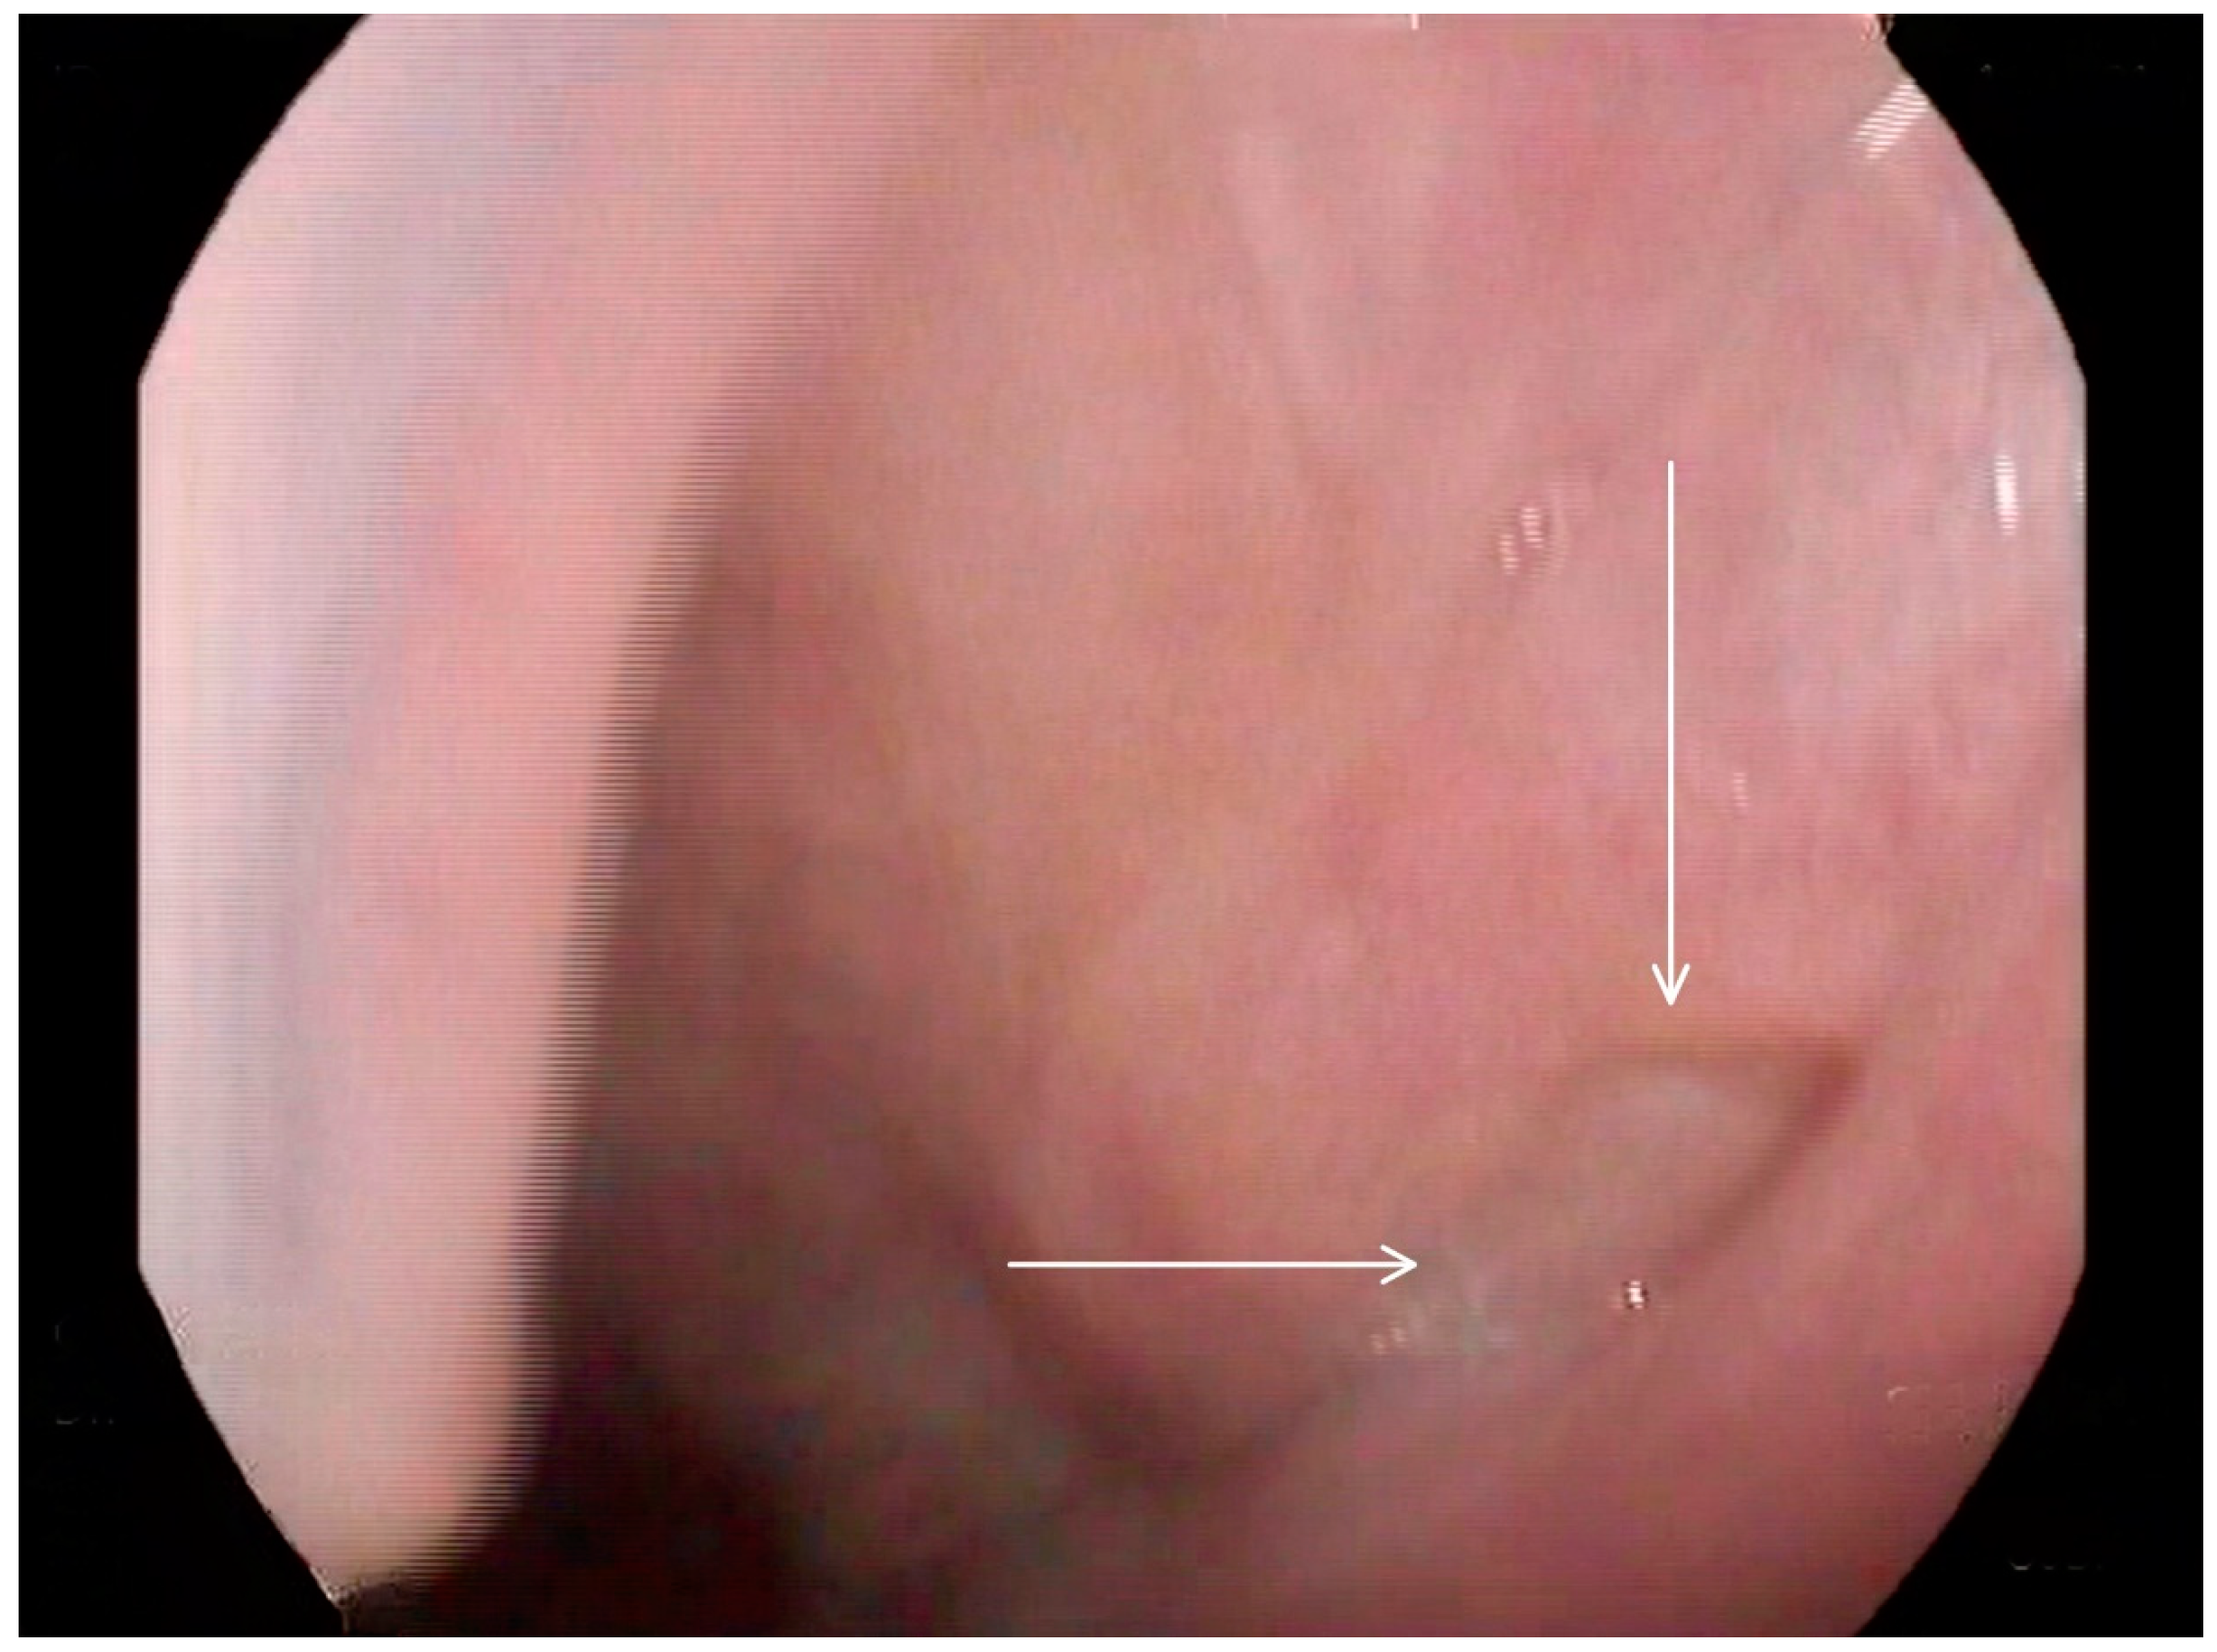

Following these findings, the ENT specialist reassessed the patient and confirmed the presence of bilateral diverticula in the buccal area and posterior pharyngeal walls, in alignment with the VFSS findings. The two diverticula were located on the right and left side inferiorly in the buccal area (Figure 3) and (Figure 4), and two were located on the right and left side superiorly in the oropharynx area. (Figure 5) and (Figure 6).

Figure 6. Selected still image captured during the FEES assessment: arrow heads pointing to the opening of a diverticulum located in the right superior aspect of the oropharyngeal area.